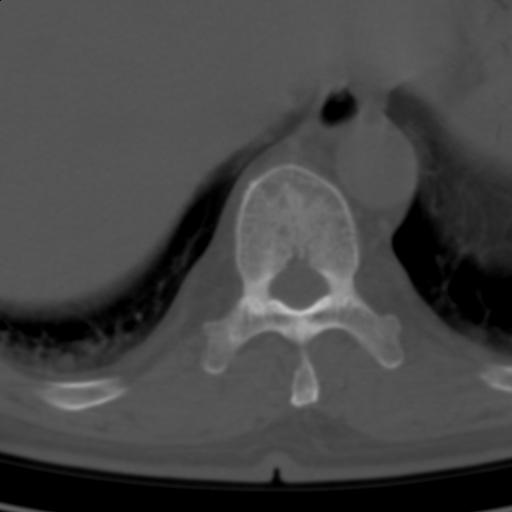

标题: CT25189:胸椎ct,请会诊!

既往食管癌,现行ct检查!

中上段食道癌,椎体轻度退变。

椎体退行性改变,食管癌。

支持中上段食道癌,椎体轻度退变,必要时做ect。